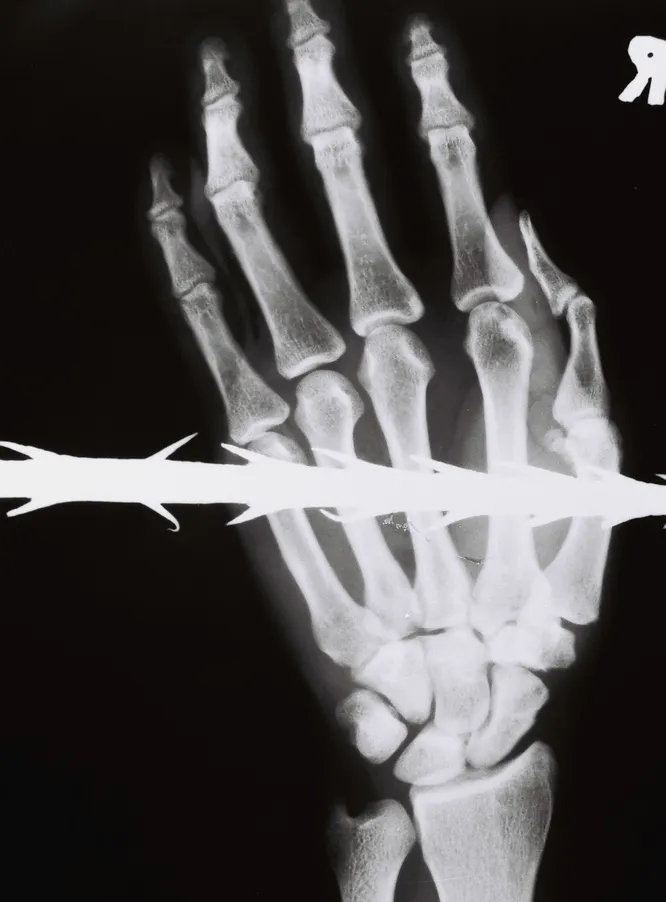

СЕВЕРНАЯ ИРЛАНДИЯ, 1988 ГОД

Колено мужчины, раздробленное осколками пули. Выстрел в коленную чашечку — одно из самых болезненных ранений. Боевики ИРА использовали его как метод наказания. Когда врачи научились лечить его последствия, в тех же целях стали практиковаться выстрелы в локти и лодыжки.